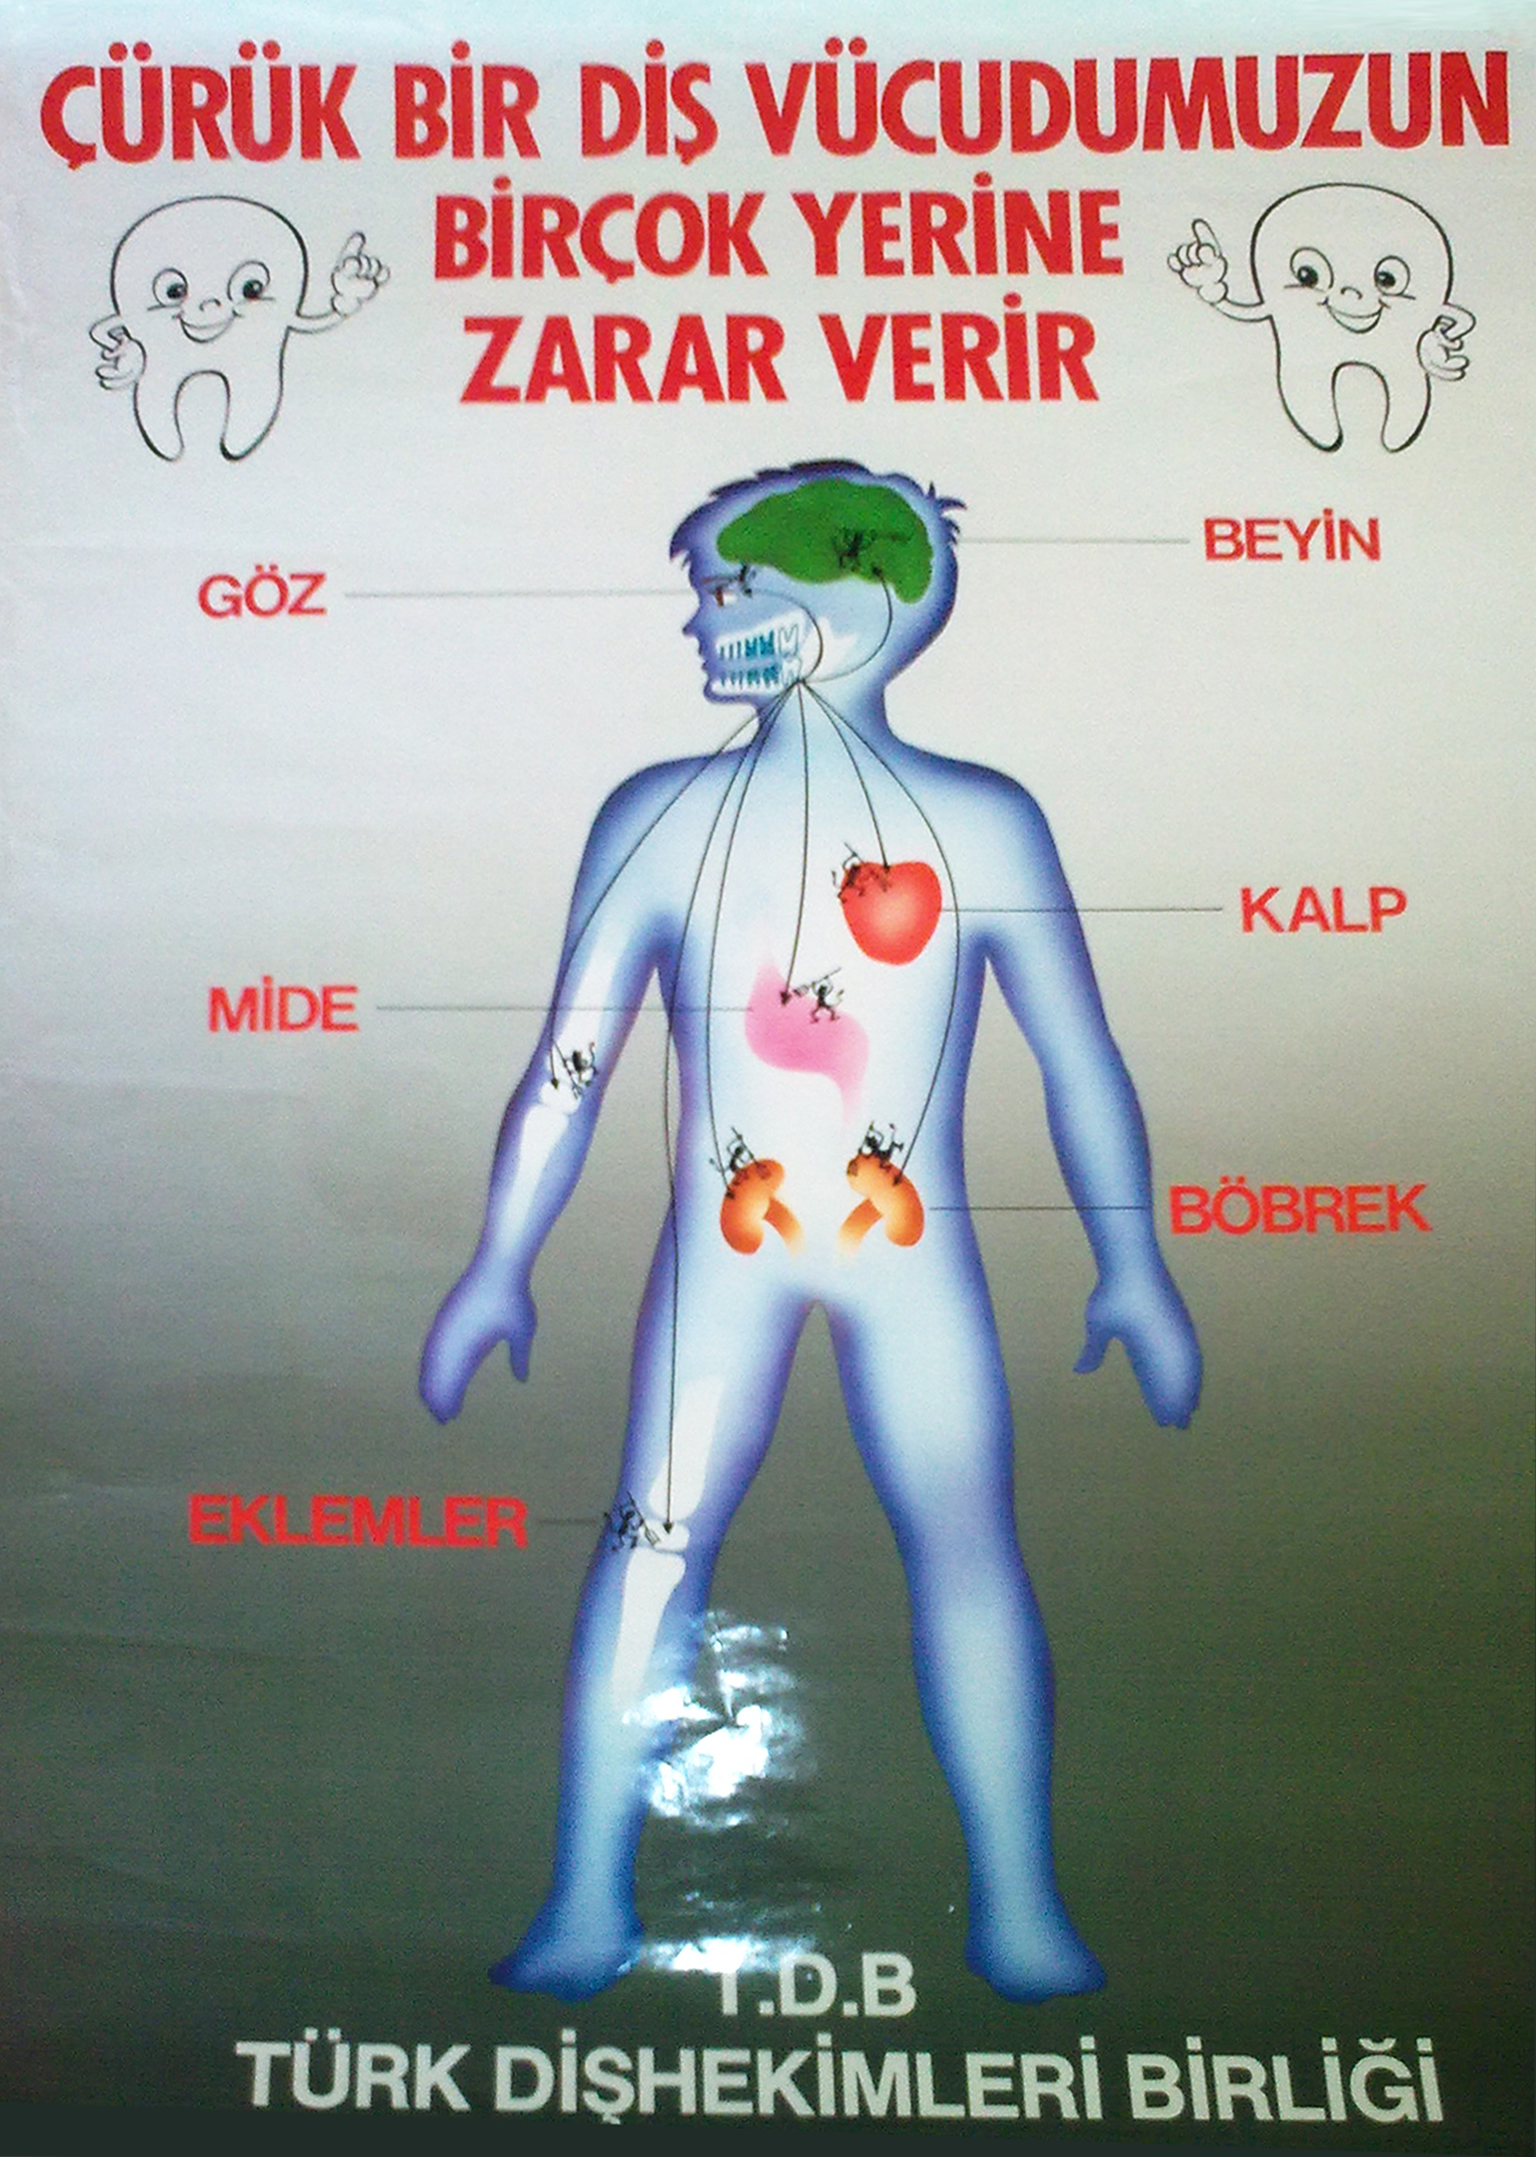

Diş çürüğü nedir? Diş çürükleri daha çok koyu renklenmelerle birlikte görülen oyuklar olarak algılanmaktadır. Önlenebilir bir hastalık olmasına karşın dünyada diş çürüğü deneyimi yaşamayan çok az insan vardır. Dişler neden çürür? Ağızda bulunan bakterilerden oluşan bakteri plağı, şekerli ve unlu yiyeceklerin ağızda kalan artıklarından asit oluşturabilmektedir. Bu asitler, dişlerin mineral dokusunu çözerek dişin minesinin bozulmasına ve sonuçta da diş çürüğünün başlamasına ve dişhekimlerinin kavite dedikleri oyuklara neden olmaktadırlar. Kimlerde daha çok çürük olur? Şekerli ve unlu yiyeceklerle bakterilerin buluşması sonucunda çürükler oluştuğuna göre herkes için bir tehlike var demektir. Ancak beslenmelerinde karbonhidratlı ve şekerli yiyeceklerin oranı çok yüksek olanlar bir de sularında florür oranı çok düşükse çok daha fazla çürük tehlikesi altındadırlar. Bakteri plağı tarafından oluşturulan asite karşı tükürük doğal bir savunma mekanizması oluştursa da tek başına çürüğü önleyemez.Tükürük akışını ve miktarını azaltan hastalıklar ya da ilaçlar da çürük oluşumunu hızlandırmaktadırlar. Bu nedenle de dişhekimleri tükürük akışını arttırdığı için şekersiz sakızları sıklıkla önerirler. Diş çürüğü önlenebilir mi? Evet. 1. Sabah kahvaltısından sonra ve akşam yatmadan önce dişlerin fırçalanması ve hergün diş ipliğinin düzenli kullanılması en etkili yoldur. Yiyecek artıkları en çok dişlerin çiğneme yüzeylerindeki girintilerde ve dişlerin birbirine değdiği ara yüzeylerde biriktiği için, diş fırçaları küçük başlı seçilmelidir. Dişlerin iç yüzeyleri, dış yüzeyleri, çiğneyici yüzeyleri ve dilin üstü fırçalanmalı ve ara yüzlerde diş ipliği kullanılmalıdır. Fırçalar, orta derecede sert ya da yumuşak kıllı olmalı ve belirli aralıklarda değiştirilmelidirler. Fırça kıllarının aşınmamış olması ve bakteri taşımayacak bir şekilde muhafaza edilmesi gerekmektedir. Asla başkasının diş fırçası kullanılmamalıdır. Diş fırçalama sırasında florürlü bir diş macunu kullanılarak, florürün diş çürüğünü önlemedeki rolünden yararlanılmalıdır. Florürlü macunlara yardımcı olarak aynı zamanda ağız kokusunu gidererek ferahlık ve temizlik hissi veren florürlü gargaralar da kullanılabilir. 2. Şekerli yiyecekleri ana öğünlerde tüketmeye çalışmak ve yemek aralarında birşey yememeye gayret etmek de diğer bir önlemdir. 3. Dişhekimine muntazam aralıklarla başvurmak bir çürüğü önlemek ya da erken yakalamada en iyi yoldur. Ayrıca sıcak ve soğuğa duyarlı dişler ya da ağrılı dişlerde veya tebeşirimsi renkte olan başlangıç çürükleri, kahverengi renklemeler ve oyuklar gibi durumlarda vakit geçirilmeden hekime başvurulması tedavinin şeklini değiştirecek ve zorluğunu azaltacaktır.  .jpg)